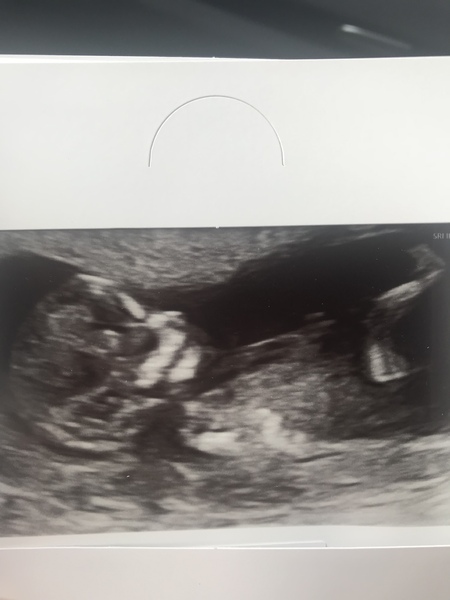

AJ89 · 30/04/2018 18:22

Had our nhs scan today, measuring 13 weeks exactly, giving a new due date of 5th November, bonfire baby! Loving the big leg. Can’t wait to find out the sex in a few weeks.

TinyPawz · 30/04/2018 18:23

Brilliant picture!!

@AJ89 Congratulations! That's a lovely pic!

Fab scan @AJ89!

@AJ89 great picture!!!

@AJ89 nice scan

@AJ89 that’s a fab pic!

@AJ89 lovely pic. ;)